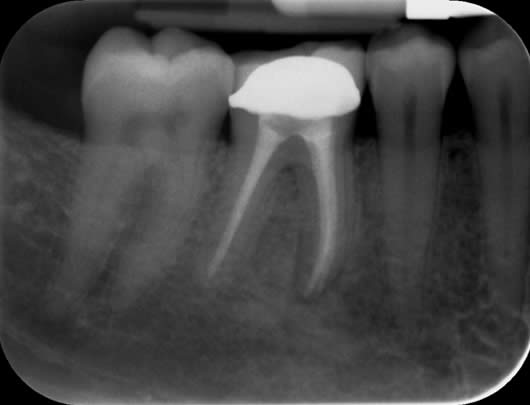

Case 4: Root canal treatment - curved canals.

Some teeth develop with acutely curved roots. These can be very challenging to treat not least because of stresses it puts on the instruments but also, it can be difficult to maintain the shape. The main challenge in this case was the acute curve in the front (mesio-buccal) root. We managed to maintain the shape after careful progression to ensure our files did not fracture.

Before treatment UL6

Following root canal treatment